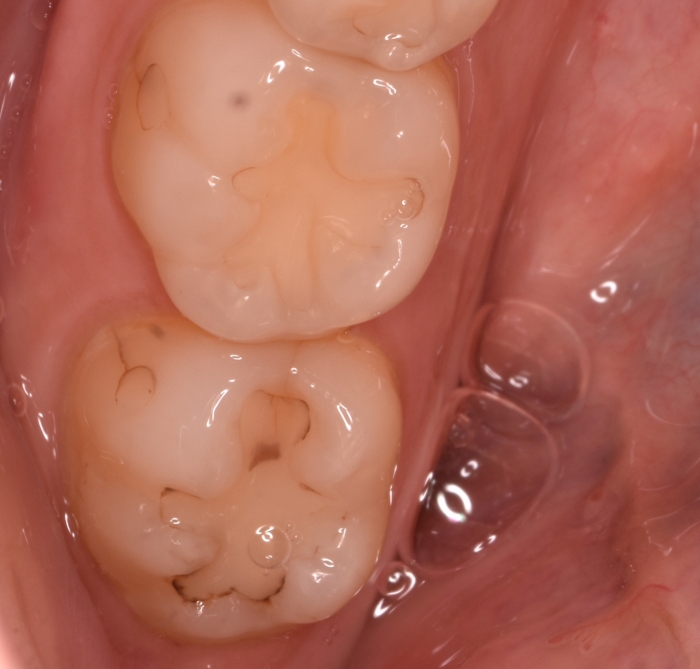

症例は,「むし歯を治して欲しい」と受診された患者さんです.冷水痛や咬合痛はなく見た目が気になるとのことでした.

古い充填物のマージンが着色してますがエナメルの範囲内にとどまり,象牙質に感染が広がっている所見はありません.

古い充填の厚みは無く,かみ合わせがきつく,摩耗が著しいです.詰め物の強度確保のため厚みをとるには健全な象牙質を大きく削り込む必要があります

かえって痛くなりそうですね.

当院の診断は

「治療が必要な状態ではありません.再治療してもおそらく冷水痛に悩まされたあげく,1年後には脱離や破折を起こすと思われます.治療のメリットが無く,経過観察がよろしいかと思います」

というお答えになります.